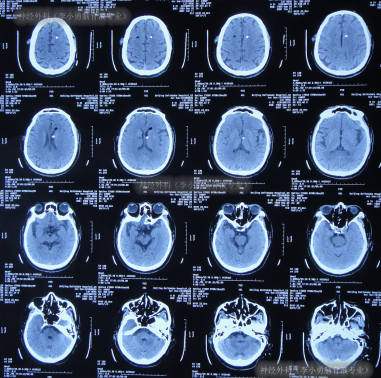

出院后3余年即2020年10月21日,第2次出现行走不稳,头晕;于是第2次就诊给予脑室腹腔分流术的医院,就诊期间出现嗜睡,查头颅CT(图-1)后给予调高分流泵压。

图-1:2020年10月21日头颅CT